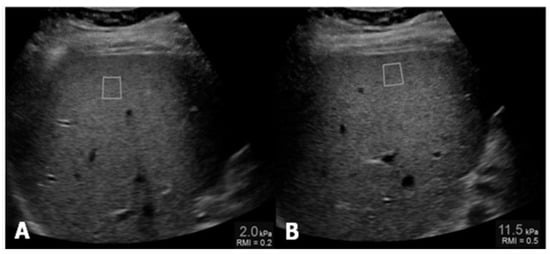

Different methods can be performed for the evaluation of liver steatosis by magnetic resonance imaging (MRI), but the most widely preferred method is based on chemical shift imaging [14,15]. This technique is based on the different precession of protons linked to water and triglyceride molecules. Two sets of gradient-echo images of the liver are obtained, and echo-time-dependent signal interference between fat and water is considered. On in-phase echo-time, water and fat signals add up and therefore, the total signal intensity is higher. On out-of-phase echo-time, water and fat signals cancel out each other and consequently the total signal intensity decreases. Healthy liver has no difference in signal intensities between the in-phase and out-of-phase images, however, in the case of fat storage, the liver signal intensity diminishes on the out-of-phase image (Figure 3). This imaging method is reliable in the absence of magnetic field non-homogeneity and iron deposition. The main drawback is that the quantity of water and fat can affect their signals. This can be managed by acquiring new images with variable T1-weighting, through the application of two flip angles. High-flip-angle imaging is desirable for uncovering small amounts of fat in tissues that include mainly water, while low-flip-angle imaging should be applied for revealing small amounts of water in fat-rich tissues [16].

Figure 3.

MR T1-weighted images with different echo times (TE) 4.2 (A) and 2.1 (B), show a marked drop of signal intensity in the out-of-phase image (B) which is a sign of severe steatosis.